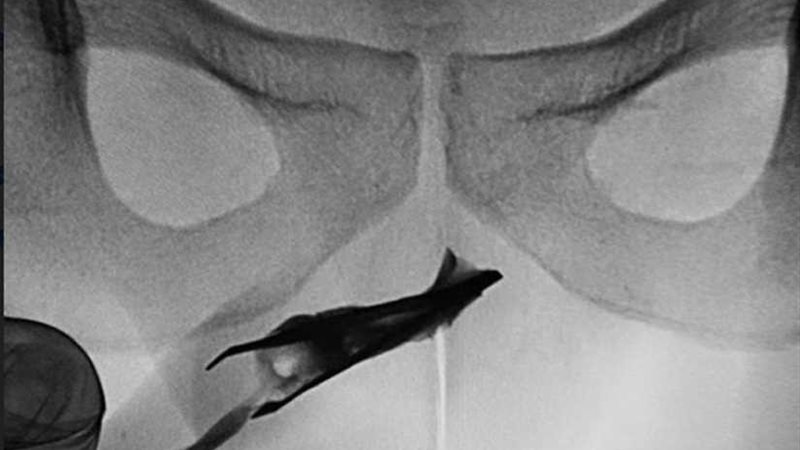

وحسبما ذكرت صحيفة "مترو" البريطانية، كشفت الأشعة السينية عن مكان وجود الملقاط ، الذي يظهر الطرف المغلق ، في مجرى البول بصلي في الأعلى.

وقام الأطباء ببذل جهود مضنية لإزالة "الملقاط" بالضغطً على جانبي القضيب لإخراج الملقاط الذى يبلغ حجمه 2.7 بوصة